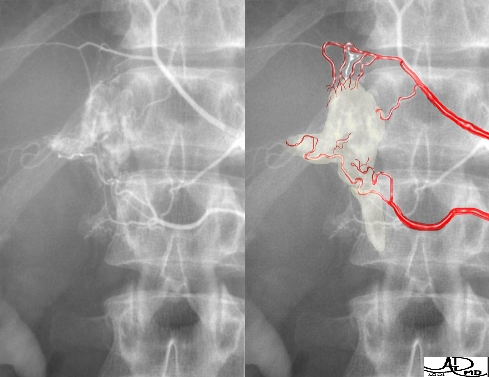

Venous Drainage – Venography |

This series of three images reflects a study called “adrenal vein sampling” which requires the simultaneous catheterization of the adrenal veins. This procedure is used to identify relative and absolute concentrations of hormone secretion from the glands to distinguish between normal, bilateral hyperplasia, and unilateral adenoma.

|

The first image shows the catheters in each of the adrenal veins. The second image is a venogram of the right adrenal vein, and the third a venogram of the left. The venogram is mainly performed to confirm that the catheter is in the correct position, because the veins, particularly the right, may be difficult to find and other small veins coming into the IVC may masquerade as adrenal veins. It is absolutely essential to be in the “right place at the right time” for this test. Courtesy of: Ashley Davidoff, M.D. |

This image is an overlay and an enlarged version of the first image above. It shows the right catheter entering the short right adrenal vein, exiting from above the right gland, and entering the IVC. The left adrenal vein, which is longer, exits from below the left gland and enters into the left renal vein. The insert of the “duel” is a reminder of the short vein on the right and the long vein on the left. Courtesy of: Ashley Davidoff, M.D. |